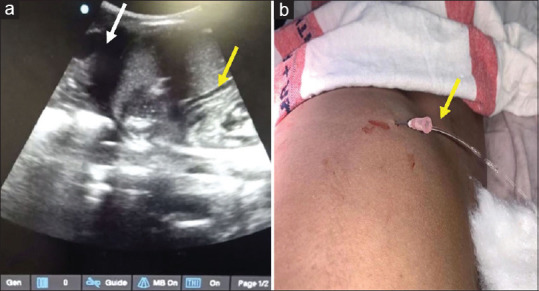

Ultrasound as a tool for rapid diagnosis of life-threatening acute compartment syndrome during percutaneous nephrolithotomy.

超声作为经皮肾镜取石术中危及生命的急性室室综合征的快速诊断工具。